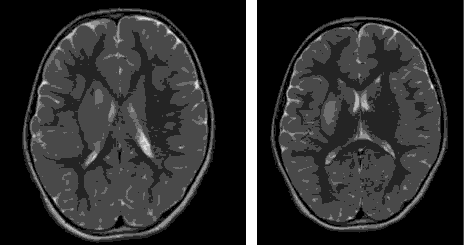

A 5-year-old girl, not known to have any medical problems, with history of minor head trauma after a fall from bed. Patient cried immediately and there was no loss of consciousness. On the following day, she was noted by parents not using her left arm and left leg. Clinical examination confirmed left sided hemiparesis with impairment of sensation on the same side. MRI of the braindone three days later, reported acute infarction involving the right globuspallidus, putamen and part of posterior limb of internal capsule. Normal MRV\MRA studies of the cerebral vessels. To rule out the possibility of an embolic heart disease, doppler ultrasound of the carotids and echocardiography was done. Lab investigations including coagulation profile (PT, PTT and INR) and thrombophilia workup (protein C and S, factor V Leiden) within normal limits. Serum amino acid analysis, carnitine levels and urine organic acid screen reported normal. She was treated by Aspirin and underwent physical therapy sessions. She showed gradual improvement in her upper and lower limb weakness over several weeks.

In our case, MRI of the brain showed an acute infarct involving the right globuspallidus, putamen and part of posterior limb of internal capsule. This explains the clinical features that are seen (Figure 1).